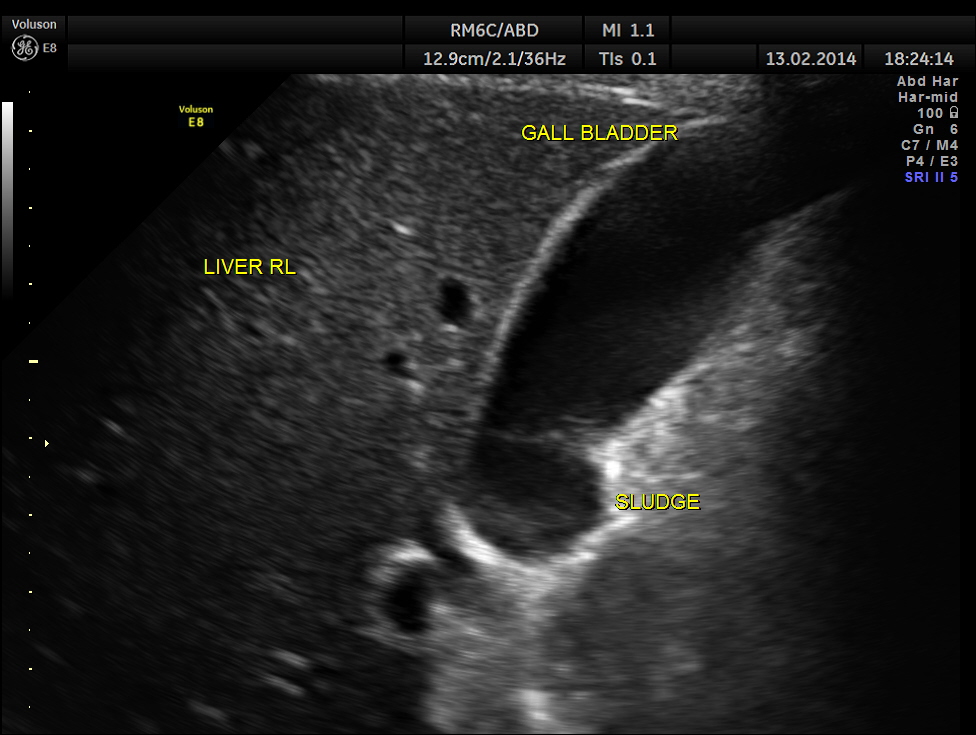

This was a 61 year old gentleman , who presented with complaints of acute abdominal distension , pain and history of constipation of 3 days duration . He showed the following findings :

distended gall bladder with sludge